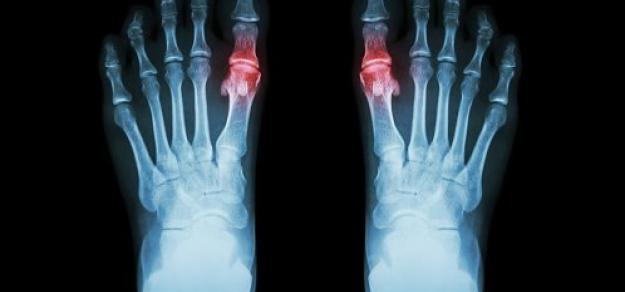

JAMA Intern Med, 8 de octubre de 2018. En este estudio de cohorte de base poblacional del Reino Unido , el uso de alopurinol en pacientes con gota no aumentó el riesgo de disminución de la función renal, y se asoció significativamente con un riesgo 13% menor a dosis de 300 mg o más por día. Lo que significa que el alopurinol no parece estar asociado con una disminución de la función renal, y los médicos deben considerar otros contribuyentes potenciales cuando se enfrentan a una disminución de la función renal en pacientes con gota.

Drug Saf , 16 de agosto de 2018 En este estudio observacional, observamos asociaciones causales probables entre el síndrome de Stevens-Johnson / necrólisis epidérmica tóxica y el uso de alopurinol, inhibidores de la ciclooxigenasa-2 y 5-aminosalicilatos, y posibles asociaciones de inhibidores de la bomba de protones, fluoxetina y mirtazapina.

CADIME;  junio de 2017 Se ha publicado la actualización de las Recomendaciones para el tratamiento de la gota de la British Society for Rheumatology de acuerdo a las evidencias posteriores a 2007 de la anterior edición. Como resumen, se pueden destacar las siguientes recomendaciones: